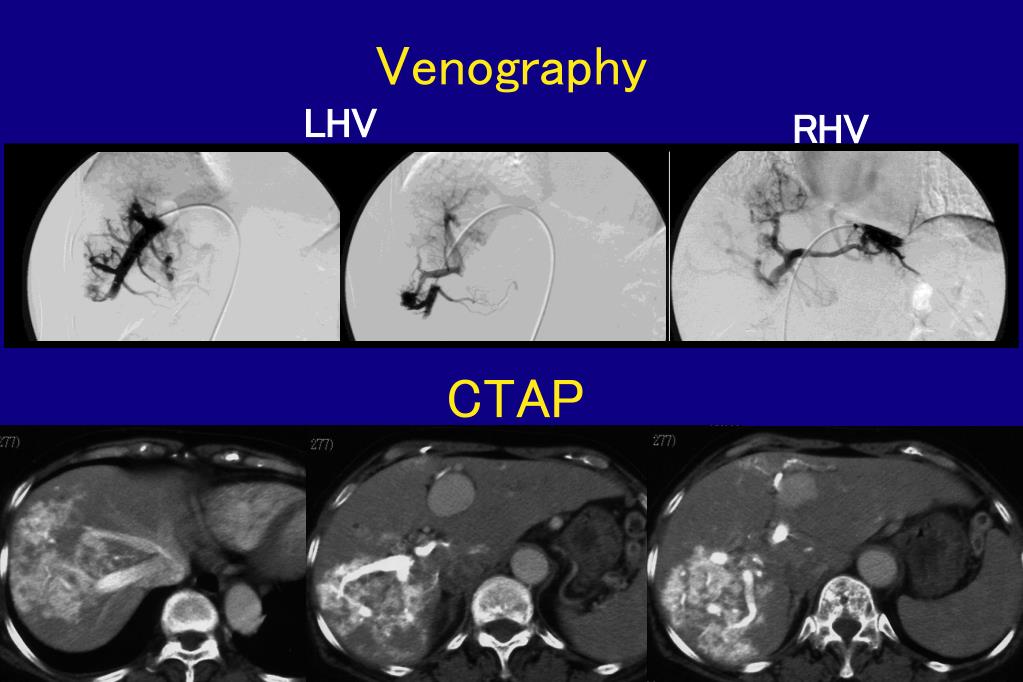

9. Venography LHV RHV CTAP